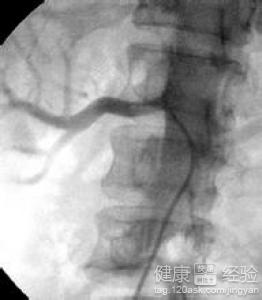

對於腎心高血壓我們可能會感到陌生的,這是繼發性高血壓的一種,與一般高血壓不同的是血壓升高是由於腎髒實質性病變和腎動脈病變引起的,分為容量依賴型高血壓和腎素依賴型高血壓,一般來說主要是由於腎動脈的病變或者受到壓迫引起的,需要我們重視起來采取積極的治療措施的,那麼腎性高血壓的治療是怎樣的呢?我來為大家解答。

1腎性高血壓屬於高血壓中比較嚴重的一種類型,一般可以通過外科手術的方式進行治療的。包括腎切除、腎血管重建以及自體腎髒移植等方式。另外還要使用β受體拮抗藥比如來輔助治療的。